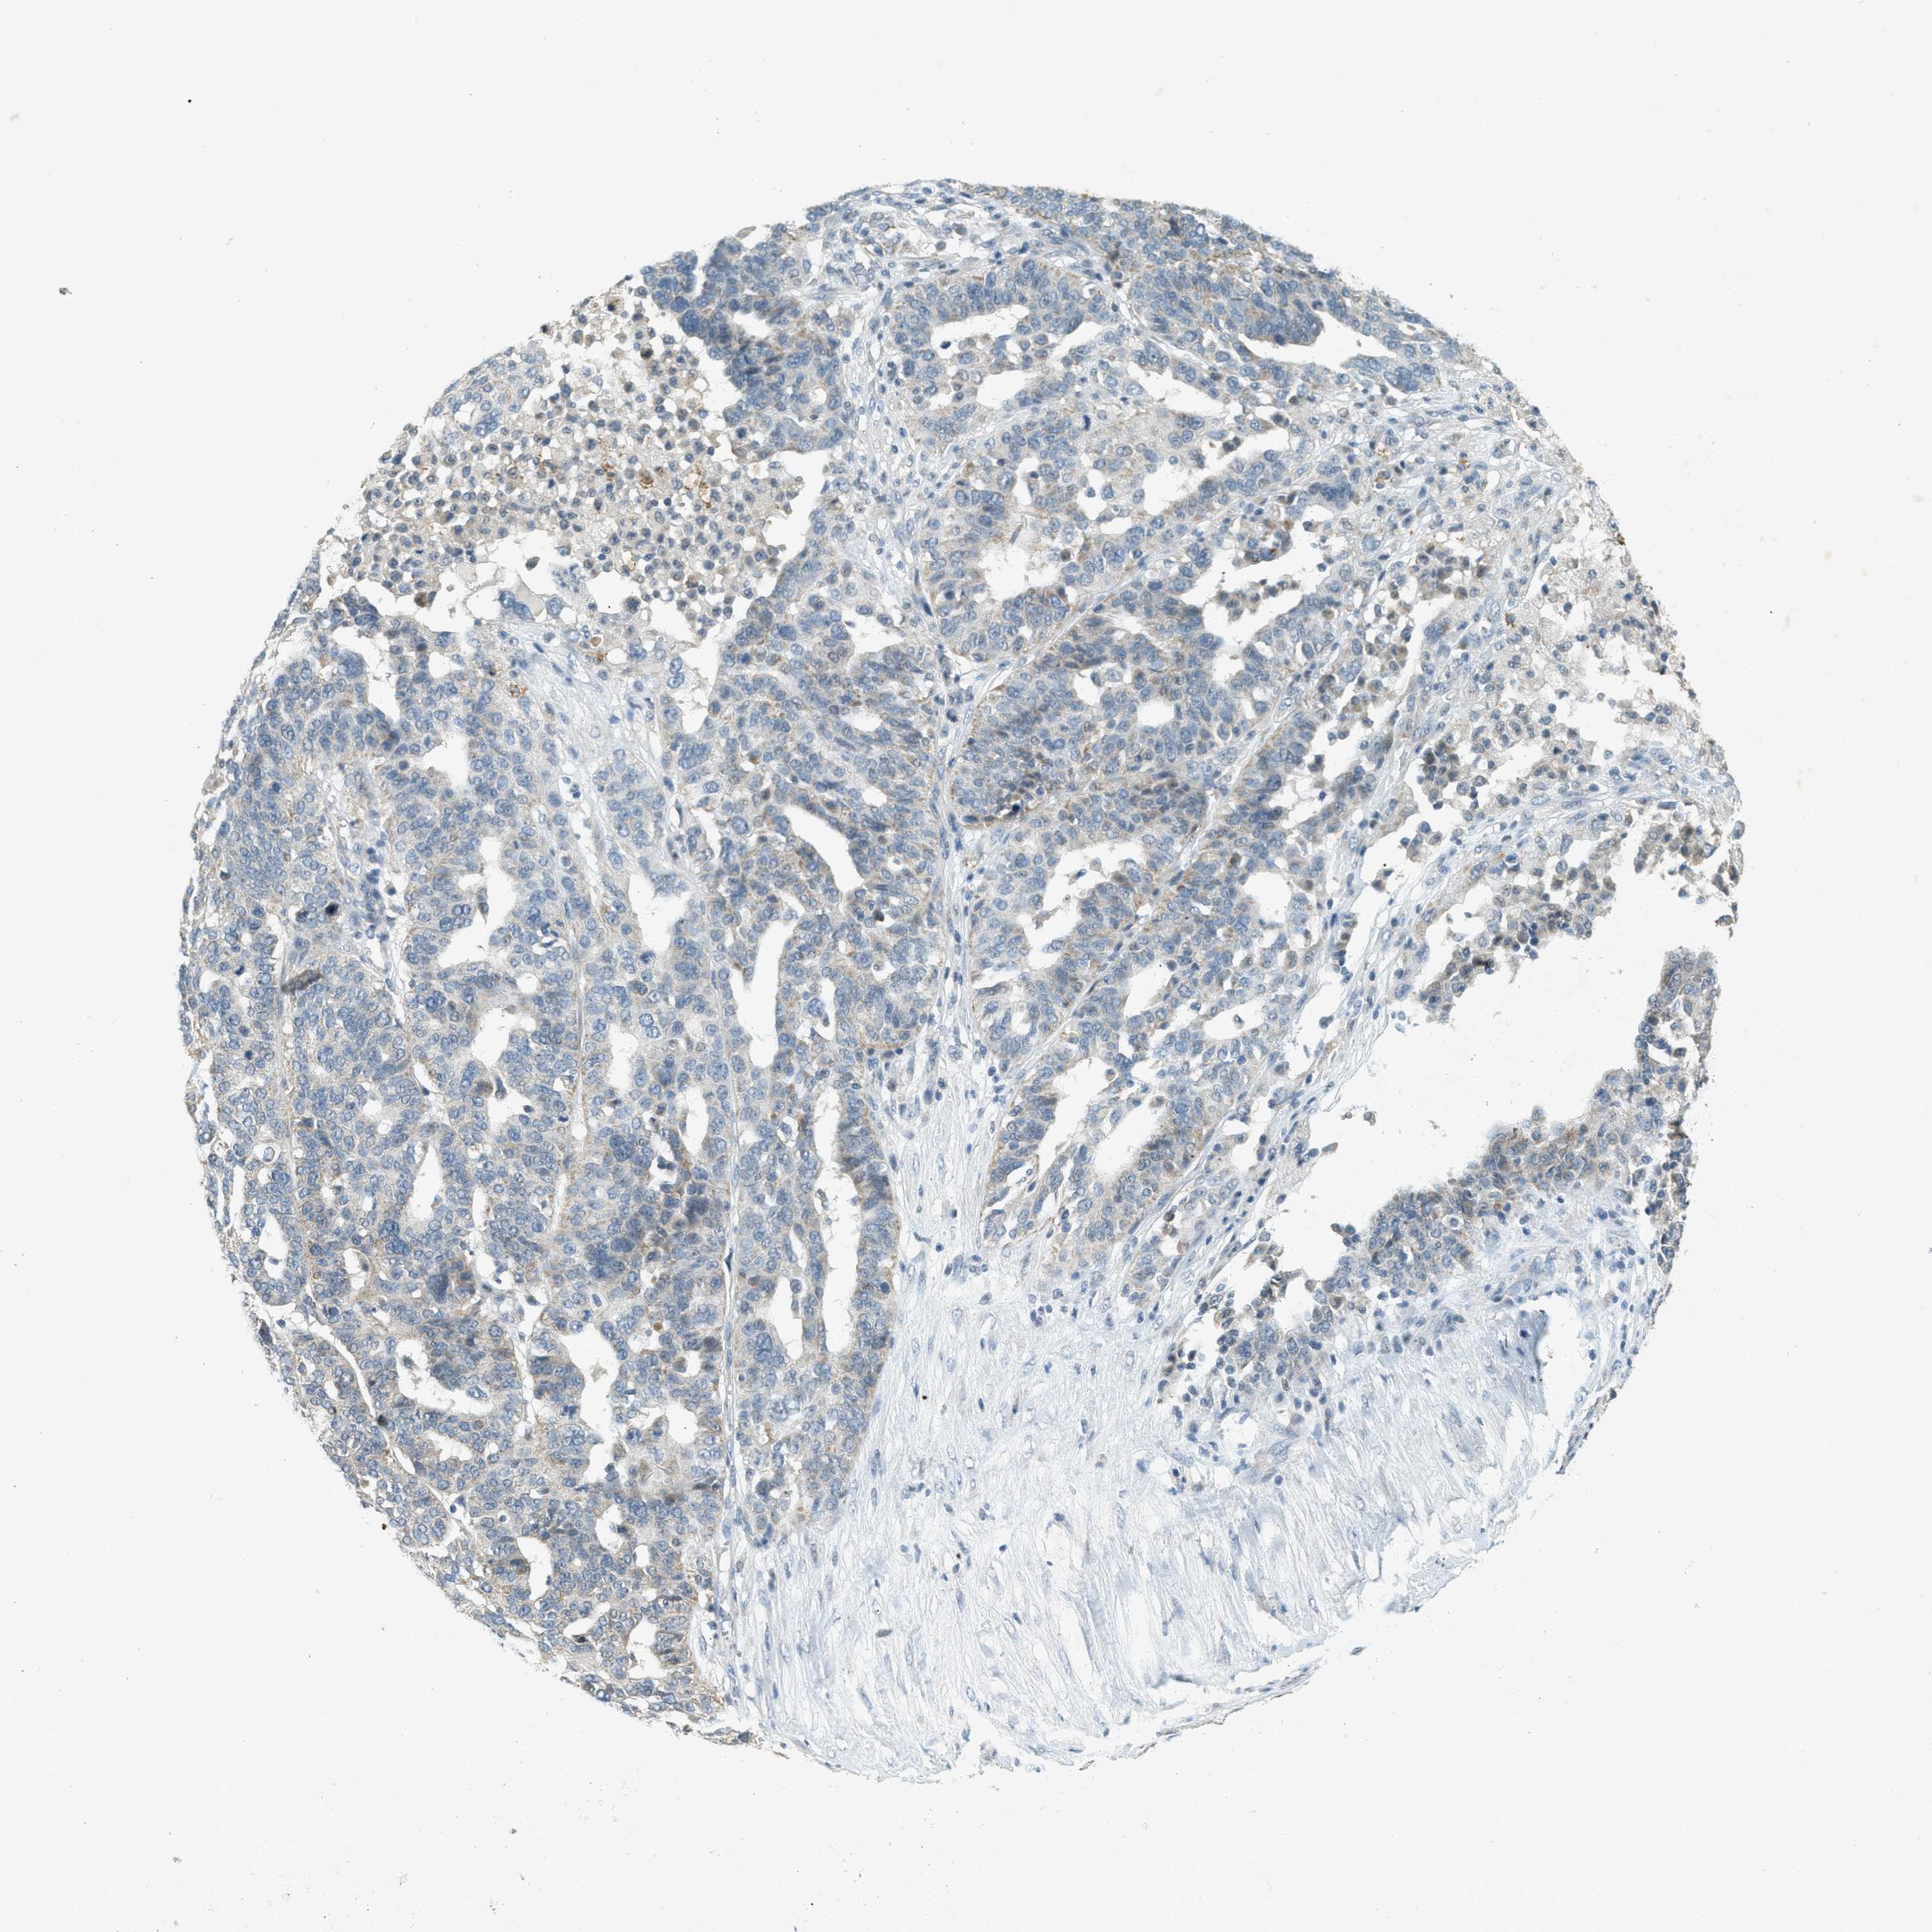

OVARIAN CANCER - Protein expressioni

A mouse-over function shows sample information and annotation data. Click on an image to view it in a full screen mode. Samples can be filtered based on level of antibody staining by selecting one or several of the following categories: high, medium, low and not detected. The assay and annotation is described here.

Note that samples used for immunohistochemistry by the Human Protein Atlas do not correspond to samples in the TCGA dataset.

Antibody stainingi

Antibody staining in the annotated cell types in the current human tissue is reported as not detected, low, medium, or high, based on conventional immunohistochemistry profiling in selected tissues. This score is based on the combination of the staining intensity and fraction of stained cells.

Each image is clickable and will lead to virtual microscopy that enables deeper exploration of all samples and also displays staining intensity scores, fraction scores and subcellular localization as well as patient and tissue information for each sample.

Antibody HPA036786

Antibody CAB017849

Cystadenocarcinoma, serous, NOS